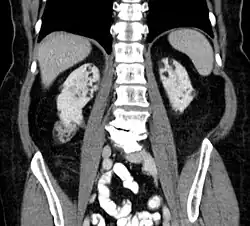

Kidneys

Between 26% and 80% of TSC patients have benign tumors of the kidneys called angiomyolipomas, with hematuria being the most frequent presenting symptom.[8] TSC angiomyolipomas differ from non-TSC angiomyolipomas in age of presentation (31.5 years vs 53.6 years), mean tumor size (8.2 cm vs 4.5 cm), and percentage of cases requiring surgical intervention (50% vs 28%).[8] Although benign, an angiomyolipoma larger than 4 cm is at risk for a potentially catastrophic hemorrhage, either spontaneously or with minimal trauma.

- Repeat MRI of abdomen every one to three years throughout life. Check renal (kidney) function annually. Should angiomyolipoma bleed, this is best treated with embolisation and then corticosteroids. Removal of the kidney (nephrectomy) is strongly to be avoided. An asymptomatic angiomyolipoma that is growing larger than 3 cm is best treated with an mTOR inhibitor drug. Other renal complications spotted by imaging include polycystic kidney disease and renal cell carcinoma.